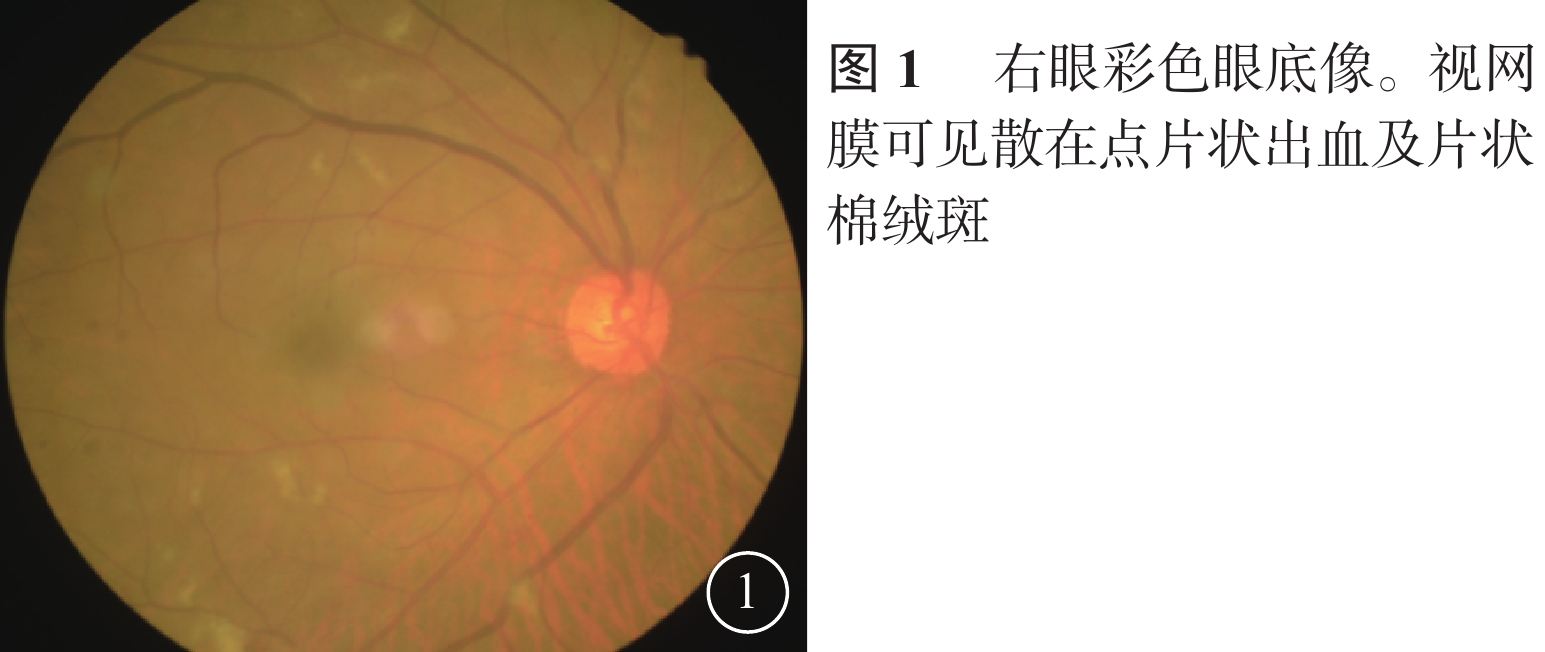

患者男,65歲。因右眼視物不見1周于2016年10月20日來我院就診。1周前無意中發現右眼視物不見,無眼紅、痛、畏光、流淚;自行使用芐達賴氨酸(商品名:莎普愛思)滴眼液滴眼無效而就診于外院。診斷為右眼新生血管性青光眼(NVG)?右眼視網膜病變(性質?);雙眼老年性白內障。既往高血壓病史8年,口服藥物治療。否認糖尿病、冠心病等其他全身病史。眼科檢查:右眼視力光感/眼前;左眼視力0.6,不能矯正。右眼眼壓17.3 mmHg(1 mmHg= 0.133 kPa),左眼眼壓12.7 mmHg。右眼前房深淺正常,周邊前房1 角膜厚度;瞳孔藥物性散大,邊緣全周可見虹膜新生血管(NVI),無后粘連;晶狀體混濁;玻璃體輕度混濁。眼底視盤邊界清楚,顏色橘紅,血管走形及比例基本正常;視網膜可見散在點片狀出血及片狀棉絨斑,黃斑中心凹反光不清(圖1)。左眼除晶狀體混濁、玻璃體輕度混濁,黃斑中心凹反光不清外,其余眼前節及眼底檢查未見明顯異常。熒光素眼底血管造影(FFA)檢查,右眼脈絡膜背景熒光充盈遲緩,視網膜動靜脈循環時間明顯延長(圖2)。光相干斷層掃描檢查,右眼后極部視網膜增厚,視網膜內層間反射信號大部分增強;左眼黃斑中心凹形態不規則。彩色超聲多普勒血流成像(CDFI)檢查,雙側頸總動脈、頸內動脈多發斑塊;右側頸內動脈管腔狹窄,約70%~99%(圖3)。頸動脈CT血管造影(CTA)檢查,顱內動脈硬化,可疑右側頸內動脈C1段重度狹窄;可疑兩側基底節區、右側丘腦腔隙性缺血灶。診斷:右眼眼缺血綜合征(OIS);雙眼老年性白內障;高血壓病。給予右眼玻璃體腔注射雷珠單抗0.05 ml治療。治療后3 d,視力數指/66 cm,眼壓15.0 mmHg;NVI完全消退。行右眼全視網膜激光光凝(PRP)治療。PRP治療后14 d檢查,右眼視力0.1;眼壓13.0 mmHg。轉血管外科行右側頸動脈內膜剝脫手術。手術后1個月復查,右眼視力0.4。FFA檢查,視網膜循環時間明顯改善(圖4)。

患者男,65歲。因右眼視物不見1周于2016年10月20日來我院就診。1周前無意中發現右眼視物不見,無眼紅、痛、畏光、流淚;自行使用芐達賴氨酸(商品名:莎普愛思)滴眼液滴眼無效而就診于外院。診斷為右眼新生血管性青光眼(NVG)?右眼視網膜病變(性質?);雙眼老年性白內障。既往高血壓病史8年,口服藥物治療。否認糖尿病、冠心病等其他全身病史。眼科檢查:右眼視力光感/眼前;左眼視力0.6,不能矯正。右眼眼壓17.3 mmHg(1 mmHg= 0.133 kPa),左眼眼壓12.7 mmHg。右眼前房深淺正常,周邊前房1 角膜厚度;瞳孔藥物性散大,邊緣全周可見虹膜新生血管(NVI),無后粘連;晶狀體混濁;玻璃體輕度混濁。眼底視盤邊界清楚,顏色橘紅,血管走形及比例基本正常;視網膜可見散在點片狀出血及片狀棉絨斑,黃斑中心凹反光不清(圖1)。左眼除晶狀體混濁、玻璃體輕度混濁,黃斑中心凹反光不清外,其余眼前節及眼底檢查未見明顯異常。熒光素眼底血管造影(FFA)檢查,右眼脈絡膜背景熒光充盈遲緩,視網膜動靜脈循環時間明顯延長(圖2)。光相干斷層掃描檢查,右眼后極部視網膜增厚,視網膜內層間反射信號大部分增強;左眼黃斑中心凹形態不規則。彩色超聲多普勒血流成像(CDFI)檢查,雙側頸總動脈、頸內動脈多發斑塊;右側頸內動脈管腔狹窄,約70%~99%(圖3)。頸動脈CT血管造影(CTA)檢查,顱內動脈硬化,可疑右側頸內動脈C1段重度狹窄;可疑兩側基底節區、右側丘腦腔隙性缺血灶。診斷:右眼眼缺血綜合征(OIS);雙眼老年性白內障;高血壓病。給予右眼玻璃體腔注射雷珠單抗0.05 ml治療。治療后3 d,視力數指/66 cm,眼壓15.0 mmHg;NVI完全消退。行右眼全視網膜激光光凝(PRP)治療。PRP治療后14 d檢查,右眼視力0.1;眼壓13.0 mmHg。轉血管外科行右側頸動脈內膜剝脫手術。手術后1個月復查,右眼視力0.4。FFA檢查,視網膜循環時間明顯改善(圖4)。